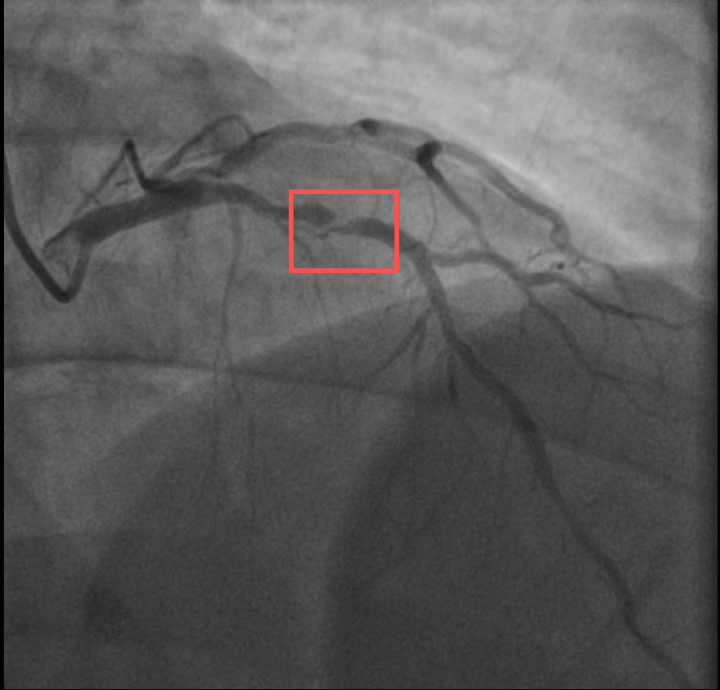

参与医治前影象图

浙江病院心(xin)血管内科的(de)医生分(fen)析,剧烈(lie)运动致(zhi)使这位患者心(xin)脏的(de)没有波动斑块碎裂,进(jin)而造成前降支近段次全闭塞。所幸送医及时(shi),孙先生的(de)身材险情被化解。

参与医治后影象图